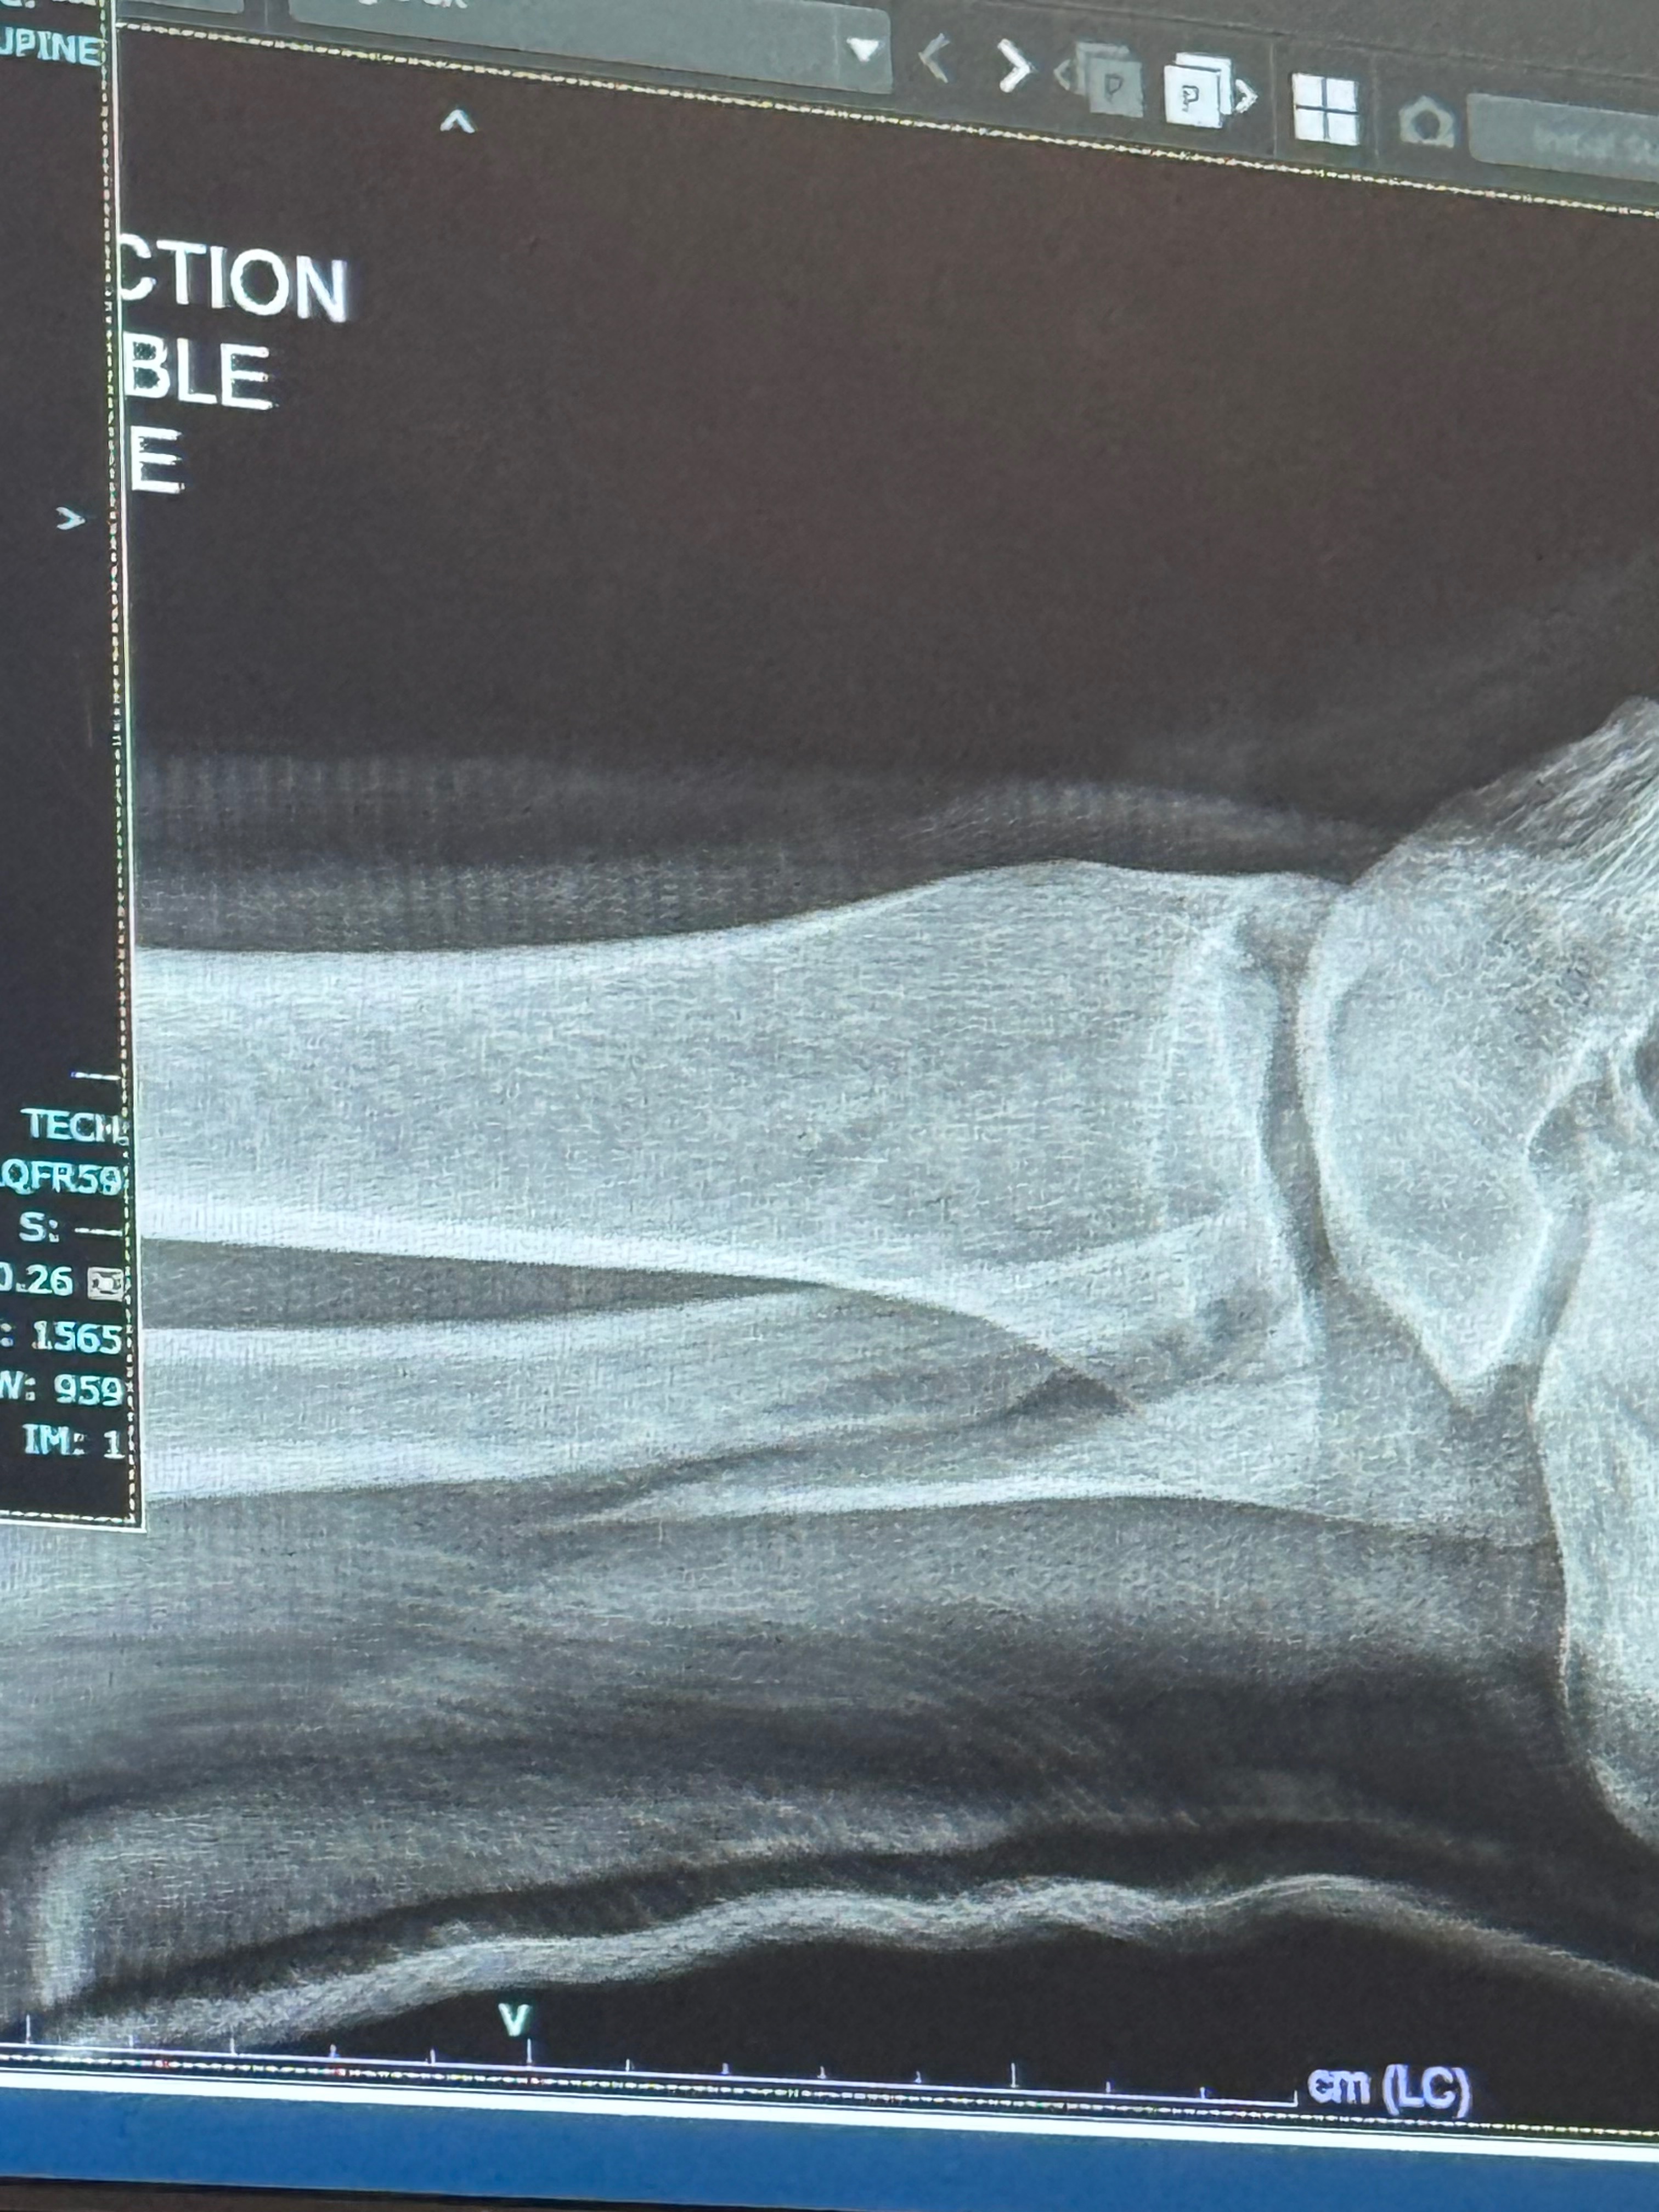

Hello we are the Garino’s, recently my husband broke his ankle quite severely which he had to take an ambulance to the hospital for as well as had to stay in patient while he had surgery to correct the bones. This has left us with a couple varying medical bills as unfortunately he does not have insurance due to a new job and he was also let go from his position due to him needing to be out of work for several months. I understand this is difficult times for everyone and I don’t expect anyone that cannot donate to do so but if you have the extra means and are willing, even a penny will help us immensely as we navigate only having one income source and paying for his medical and necessary appointments such as therapy. Thank you for taking the time to read this, have a great day.